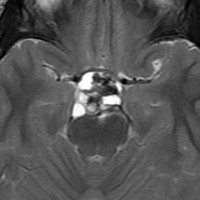

この子の症状は頭痛だけ。両親はなぜ気づかなかったのかと疑問を持ちますが,巨大になるまで症状が出ないこともあるのです。左のCTで腫瘍の周囲にバラバラと白い点状の石灰化があるので診断できます。左の視床下部から発生したクラニオでした。開頭手術しますが超高難易度です,怖いです (┯_┯) 複数回開頭手術になりましたが結果的に全摘出できています (by Dr 山本哲哉)。